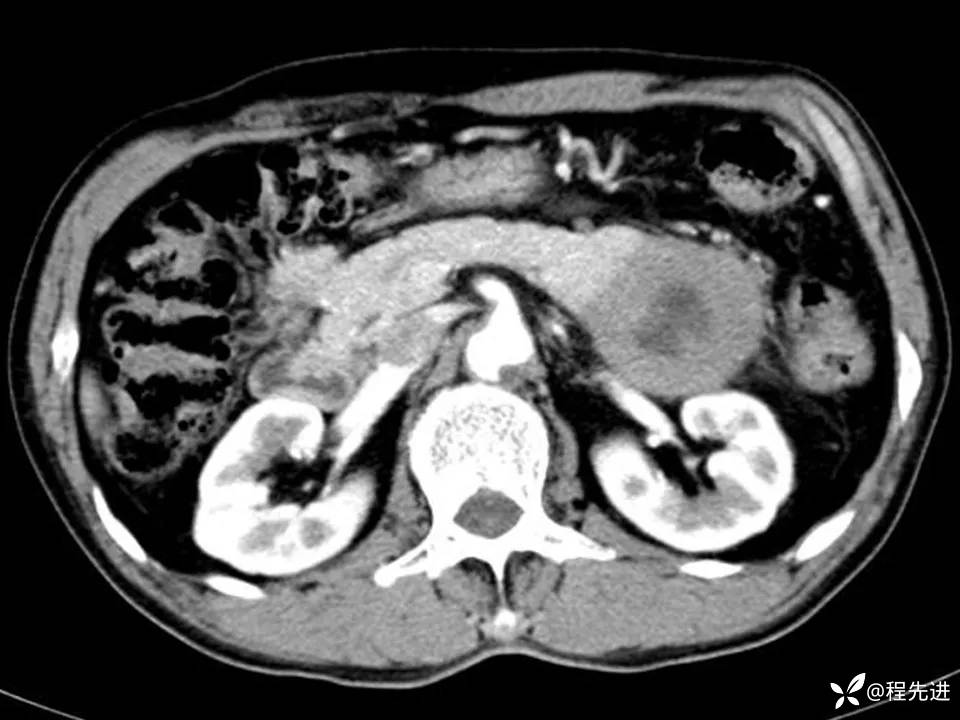

患者性别:男

患者年龄:61岁

简要病史:体检发现胰腺占位

实验室检查:(-)

CT平扫+增强: